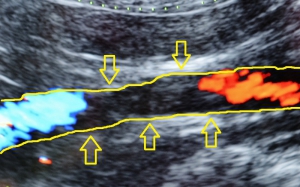

腹部の超音波検査では大動脈の中に血栓が確認できることもあります。左下が血栓を中心に観察した血流のドップラーエコーによって左右の着色部位には、青→赤の血液の流れがあること、その間の黒い部分は血栓によってその流れが遮断されていることを示しています。右下に見やすいように血管の模式図を重ねてありますが、黄色矢印に囲まれた部分が血栓を示しています。(左が頭です。)